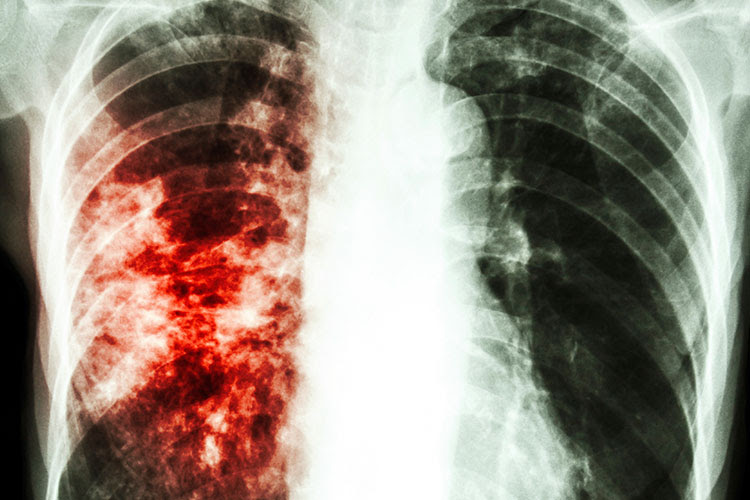

La influenza, conocido como gripe (gripa severa), es una enfermedad

viral infecciosa que afecta al sistema respiratorio superior, incluyendo

los pulmones, la garganta y nariz. Es uno de los problemas médicos más

habituales que hay, afectando a personas de todo el planeta. Los

síntomas comunes de la gripe son: secreción nasal, estornudos

repetitivos, dolor de garganta, congestión de los conductos nasales,

dolor de cuerpo, cefalea, fiebre alta, tos seca, debilidad y pérdida del

hambre, sueños con pesadillas, etc.

Es enormemente infecciosa y se extiende velozmente de una persona a otra.

Una persona que tenga gripe, debe estar lejos de los niños pequeños y las

personas mayores que tengan el sistema inmunológico bajo.

Es esencial iniciar el tratamiento tan pronto como aparezcan los síntomas,

ya que se corre el riesgo de conllevar a otras dificultades de salud como

infecciones de oído, neumonía y bronquitis. Los fármacos anti-virales

recetados pueden calmar los síntomas.

Por lo que los antídotos caseros simples pueden calmar síntomas leves